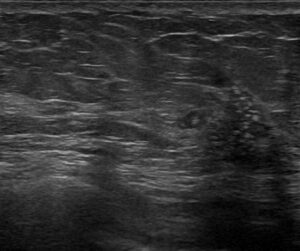

しっかり見えるぅぅぅーーー

点状高エコー+低エコー域+小嚢胞が確認出来て、